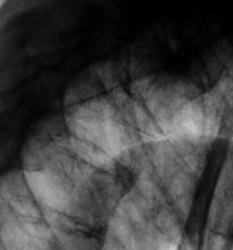

И на фоне тени фокуса "получили" отображение полости распада.

А можно-ли было "ЭТО" получить "без цифры", а при использовании аналоговой технологии? Ответ очевиден.